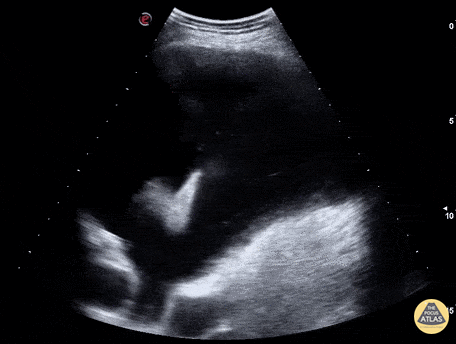

Pulmonary - Dove in Pleural Fluid

WCUME 2017 Submission for "Creative Caption" "In these days of violent extremist and warmongers, can it be a a good omen to find a dove flying in the pleural fluid?" Marco Garrone, MD - Torino, Italy